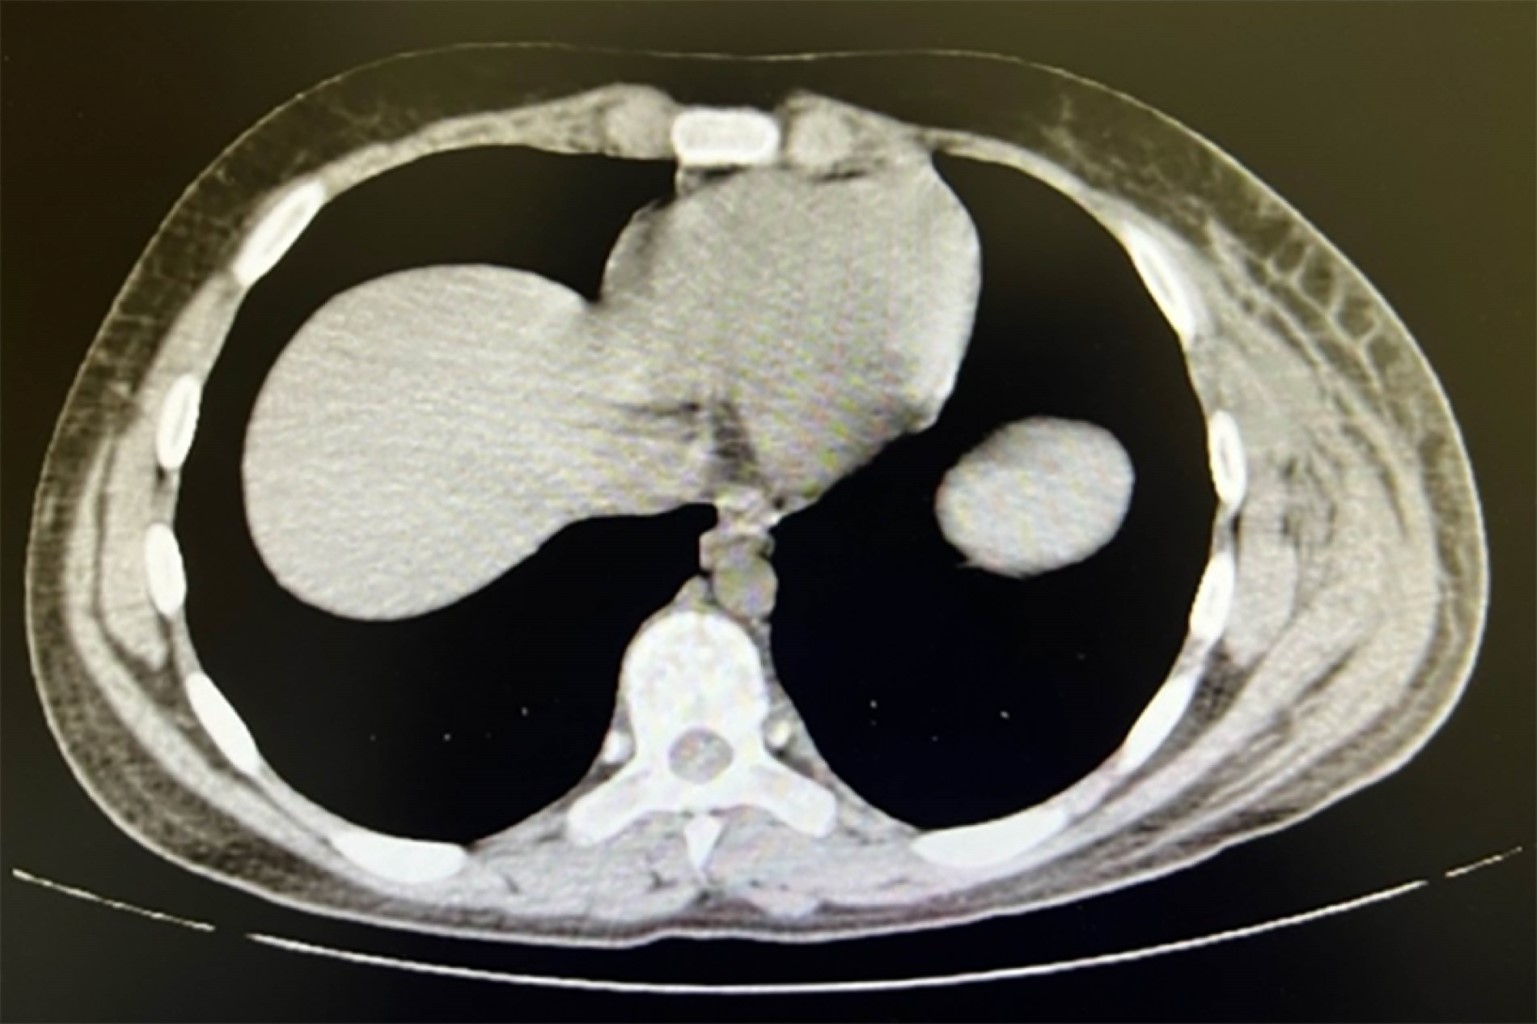

Se solicitan estudios de laboratorio al ingreso con biometría hemática que reporta hemoglobina 14.4 g/dL, hematocrito 43.1%, leucocitos 11,300 × 103 mm3, neutrófilos 10,200 × 103 mm3, linfocitos 600 × 103 mm3, monocitos 500 × 103 mm3, plaquetas 120,000 × 103 mm3, proteína C reactiva 44.2 mg/dL; pruebas de funcionamiento hepático con aspartato aminotransferasa 35 U/L, alanina aminotransferasa 39 U/L, bilirrubina total 1.4 mg/dL, creatinina 2.5 mg/dL, urea 113 mg/dL, glucosa 118 mg/dL. En la microscopia del hemocultivo periférico, con desarrollo a las 24 horas, se observaron dos colonias de cocos grampositivos en racimos y en cadenas (Figura 2). Tomografía de abdomen con aumento de volumen en tejido celular subcutáneo y aparente colección y/o hematoma a nivel de la pared anterolateral izquierda de abdomen (Figura 3).